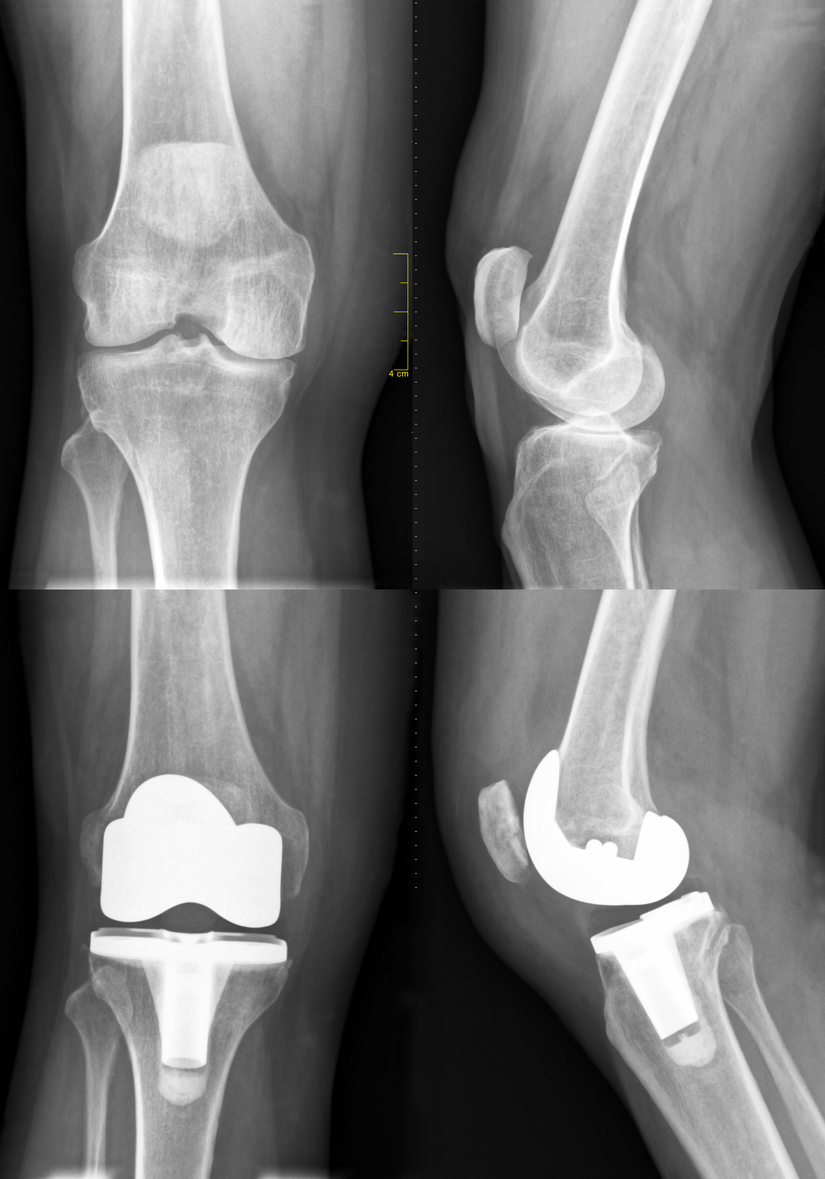

Knee X-ray image before and after a total knee replacement operation. The diseased knee joint (damaged cartilage) is replaced with artificial material (White parts = prosthesis). Frontal view and side-view.

Total Knee Replacement Surgery

If you or your loved one is experiencing knee pain that keeps you from doing the things you love, it’s time to talk to our joint replacement surgery experts at Riverside. We provide a range of solutions that will improve your mobility and alleviate your pain.

Learn More About the Knee and About Total Knee Replacement Surgery

Learn the Difference Between a Partial vs. Total Knee Replacement